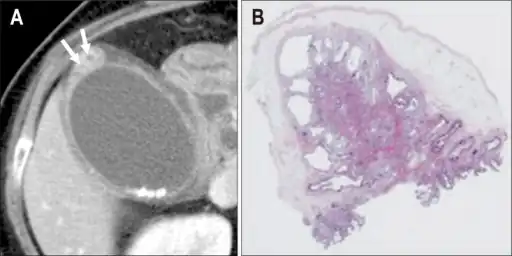

Individual with adenomyomatosis a) Axial computed tomography image b) photomicrograph -

On CT scan, it may show rosary sign, showing mucosal epithelium with intramural diverticula.[9]

Magnetic resonance imaging also plays an important role in the diagnosis of Rokitansky–Aschoff sinuses.[10] In fat-suppression MRI, RAS present with small, rounded, high signal intensity foci, called “pearl necklace sign”.[9]